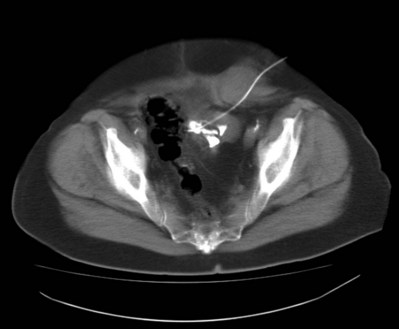

Virtually all patients who undergo SWL for renal stones demonstrate hematuria after approximately 200 shockwaves. Hematuria is so common that it may be considered an incidental finding, and its severity is rarely of concern. Although hematuria was initially considered to be a consequence of irritation of the urothelium as stones were fragmented by shockwaves, it is now known that such is not the case. Detailed morphologic studies have demonstrated that shockwaves rupture blood vessels and can damage surrounding renal tubules (Fig. 48–24). SWL is now known to induce such structural changes in the treated kidney in the majority, if not all, SWL patients, regardless of the type of lithotripter employed (Table 48–9).

Figure 48–24 Macroscopic photomicrograph of a coronal section through the kidney of a juvenile pig (about 6 weeks old) treated with 2000 shocks at 24 kV by an unmodified Dornier HM3 lithotripter and examined 4 hours after treatment. The region of intraparenchymal hemorrhage has been colored red by an automated computer color recognition program. Note that the lesion involves multiple papillae and in some regions extends through the cortex to the renal capsule, where a subcapsular hematoma may develop.

There have been reports of moderate to severe renal injury occurring after SWL, generally manifesting as a hemorrhagic event. Hematoma rates range from less than 1% up to as high as 20%, depending on the type of lithotripter used and the treatment parameters employed, as well as the radiographic modality and timing of imaging follow-up. In addition, the later generation lithotripters that have small focal areas and extremely high peak positive pressures are reported to produce higher clinically significant hematoma rates (3% to 12%), a trend that is worrisome (Thuroff et al, 1988; Ueda et al, 1993; Kohrmann et al, 1995; Piper et al, 2001). Several risk factors for the development of a post-SWL hematoma have been identified (Table 48–10). Dhar and associates (2004) reported that the probability of a subcapsular hematoma increased 2.2 times for every 10-year increase in the patient’s age. Knapp and associates (1988) found patients with existing hypertension to be at increased risk for the development of perinephric hematomas as a consequence of SWL. In particular, those patients having unsatisfactory control of their hypertension at the time of SWL had the highest incidence of hematoma formation. Additional risk factors for hemorrhage were diabetes mellitus, coronary artery disease, and obesity, all of which suggest a link to a vascular disorder. The appearance of renal hematomas can range in severity from a mild contusion localized within the renal parenchyma to a large hematoma (Fig. 48–29) associated with severe bleeding, possibly necessitating blood transfusion or rarely even angiographic embolization. Although some hematomas may persist for many months to years, it has been reported that most resolve within weeks and without long-term sequelae.